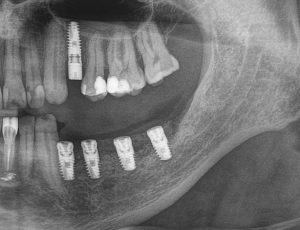

Для этого мы сделали КЛКТ:

И КЛКТ показала нам, что с имплантатами и окружающей костью всё зашибись. Через 12 лет после операции, отсутствия наблюдения, пофигизма в замене временных коронок! Нужны ли тебе еще какие-нибудь доводы в пользу долгосрочной эффективности метода?

Серия контрольных снимков на этапах: